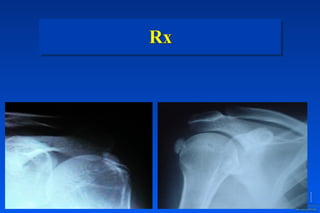

Rx

✓ Morfología ósea

✓ Calcificaciones

✓ Espacios articulares

✓ Tejidos blandos?

Muestra directa de

patología traumática o

degenerativa ósea

Evidencia de fracturas o de luxaciones

Visualización de la degeneración del

artrósica

Muestras directas de Trauma o de Artrosis

Solamente muestras indirectas de

inestabilidad y patología del

manguito